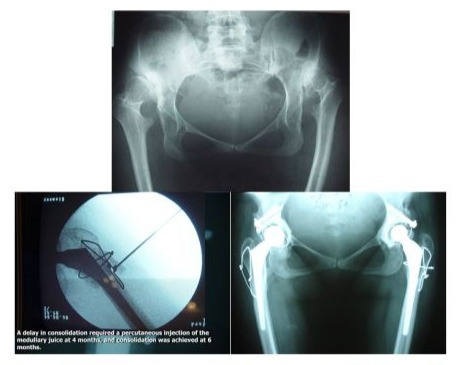

In this study, we present only the severe cases: type III - IV Crowe, type C Hartofilakidis, Eftekhar stage C and D, and type 2 and 3 of our classification. Forty-five hips were classified as type III, C Eftekhar, and seventy-seven hips were classified as type D Eftekhar, IV Crowe. Our classification showed that 101 were stage III and 21 were stage II. For the acetabulum, the technique remains the same, we use cemented prostheses. We resorted to the reconstruction of the cotyl with a massive graft, structuralized fixed by 2 screws. When we have not had prostheses with a small cup and when more than 20% of the cup remains uncovered. The mean age of the patients was 42 years (26-76 years). All patients have a minimum follow-up of 3 years. These cases belong to stage 3 of our classification. Forty-five hips were classified as type III Crowe, C Eftekhar, and seventy-seven hips were classified as type D Eftekhar, type C Hartofilakidis, IV Crowe. According to our classification, 82 were in stage III and 21 were in stage II. Preoperatively, the Merle D’Aubigne-Postel score of these 122 hips was 4. Postoperative results were very good in 41 hips (67,21%) of the first lot of operations and in 44 hips of the second lot of operations (72,13%), good in 17 hips of each lot (27,86%). Modest results were obtained in 3 hips on the first lot (4,91%) due to the non-union cases who necessitate the revision of the greater trochanter. The elongation obtained varied between 4,5 and 8 cm without any case of paralysis of sciatica. We did not do traction preoperatively. We did not have any cases of prosthesis lust in these 2 series. The use of this technique prevents the lack of supply.A delay in consolidation, of the femoral osteotomy on the second lot, required a percutaneous injection of the medullary juice at 4 months, and consolidation was achieved at 6 months (Figure 4).

Figure 4: Bilateral case of high dislocated hips, THA on high dislocated hips by triple femoral osteotomy, percutaneous injection of medullary juice help the delay of consolidation at 6 months.